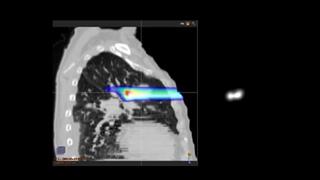

Proton Therapy

About Proton Therapy

Advantages of Proton Therapy - Willis Knighton Cancer Center

Dr. Lane Rosen Discusses Proton Therapy at the Willis Knighton Cancer Center